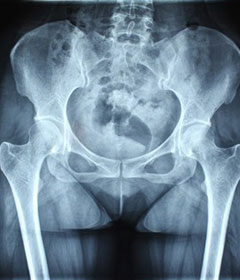

强直性脊柱炎的疾病在男性当中产生的几率是很高的,是比较多见的风湿病症,患者产生疾病的年龄段主要控制在十几岁之间,疾病产生的初期表现不是很明显,经常出现了被患者所忽视的情况,还有部分的患者会由于病症治疗不当导致了疾病难以得到有效的控制,给病...[详细] 2024-10-06

强直性脊柱炎的疾病产生和很多因素之间都是有关联的,患者的生活水平对于病症的产生都是会造成影响的。那么,疾病产生之后,就要能尽早的进行病症的诊断和治疗,避免病症产生继续的加重或者是蔓延。我院的专家指出,患者只有尽早的了解到病症是如何产生的,...[详细] 2024-10-06